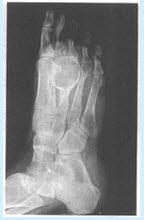

患者,女,21岁。1年前右足外伤,近日感觉右足疼痛。X线片见下图:

(单选题)该病最可能的诊断是()

A:动脉瘤样骨囊肿